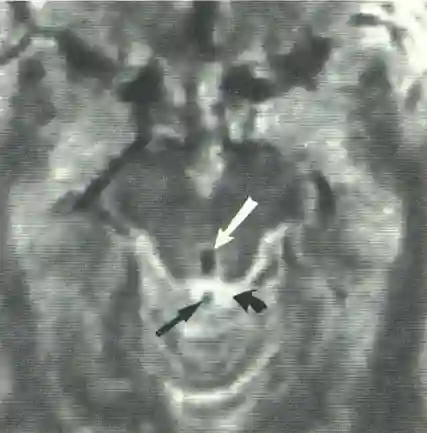

Axiales T2 MRI Bild. Es zeigt sich im Aquädukt ein Flow Void Signal (weißer Pfeil). Der Liquor in den Zisternen ist hell (gekrümmter schwarzer Pfeil). Der Blutfluß in der Vene (schwarzer gerader Pfeil) zeigt sich ebenfalls dunkel mit einem Flow Void Signal. Abbildung adaptiert von Sherman et al.